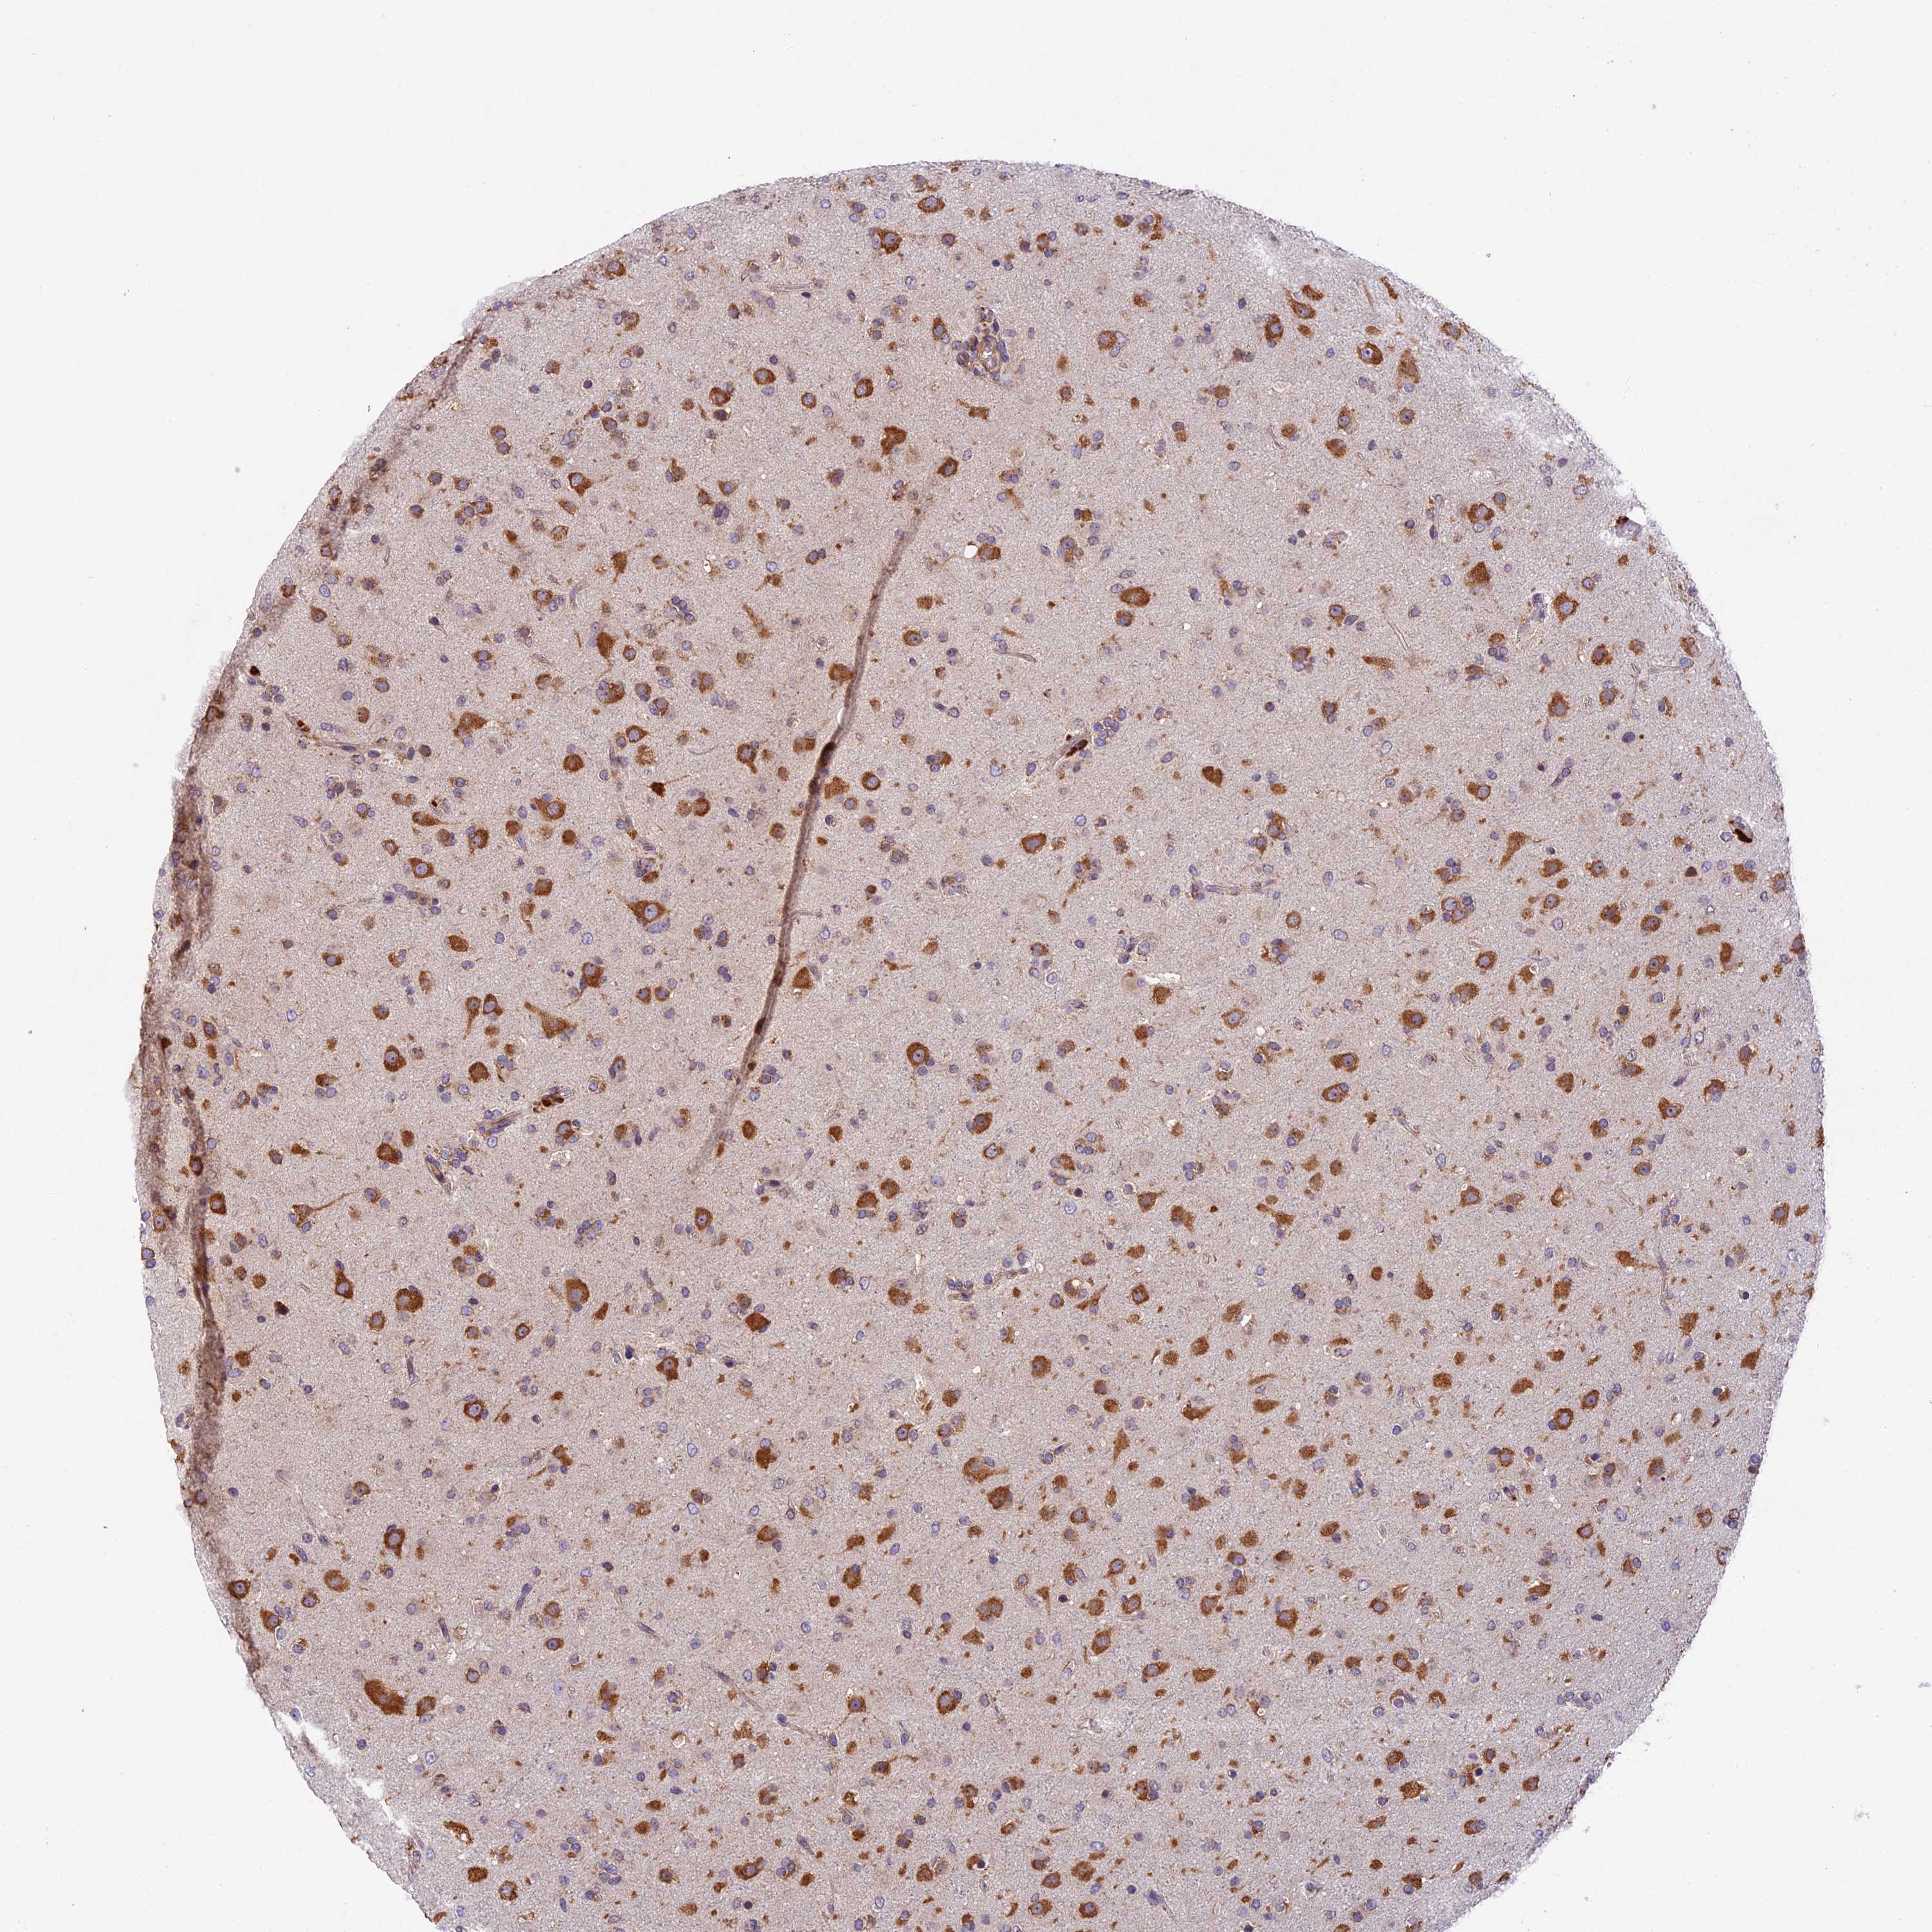

GLIOMA - Protein expressioni

A mouse-over function shows sample information and annotation data. Click on an image to view it in a full screen mode. Samples can be filtered based on level of antibody staining by selecting one or several of the following categories: high, medium, low and not detected. The assay and annotation is described here.

Note that samples used for immunohistochemistry by the Human Protein Atlas do not correspond to samples in the TCGA dataset.

Antibody stainingi

Antibody staining in the annotated cell types in the current human tissue is reported as not detected, low, medium, or high, based on conventional immunohistochemistry profiling in selected tissues. This score is based on the combination of the staining intensity and fraction of stained cells.

Each image is clickable and will lead to virtual microscopy that enables deeper exploration of all samples and also displays staining intensity scores, fraction scores and subcellular localization as well as patient and tissue information for each sample.

Antibody HPA041880

Antibody HPA054709

Staining

High

Medium

Low

Not detected

Intensity

Strong

Moderate

Weak

Negative

Quantity

>75%

75%-25%

<25%

None

Location

Nuclear

Cytoplasmic/membranous

Cytoplasmic/membranous,nuclear

Glioma, malignant, High grade

Glioma, malignant, Low grade